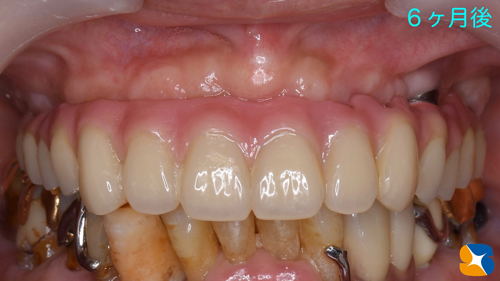

上アゴの骨が痩せ細り、インプラントも無理だと諦め、永年、入れ歯で苦労されてきた患者様のその後の結果をお知らせします。

その後、5本のインプラントは確実に定着してくれていましたので、型取りを行いました。

寸分の狂いや隙間が生じないように、丁寧かつ慎重に様々な工程を繰り返しながらネジで完全固定タイプの入れ歯を作成していきます。

完成したネジで完全固定タイプの入れ歯

ネジで完全固定タイプの入れ歯をいよいよ装着していきます。

この夏から使用を始めました。